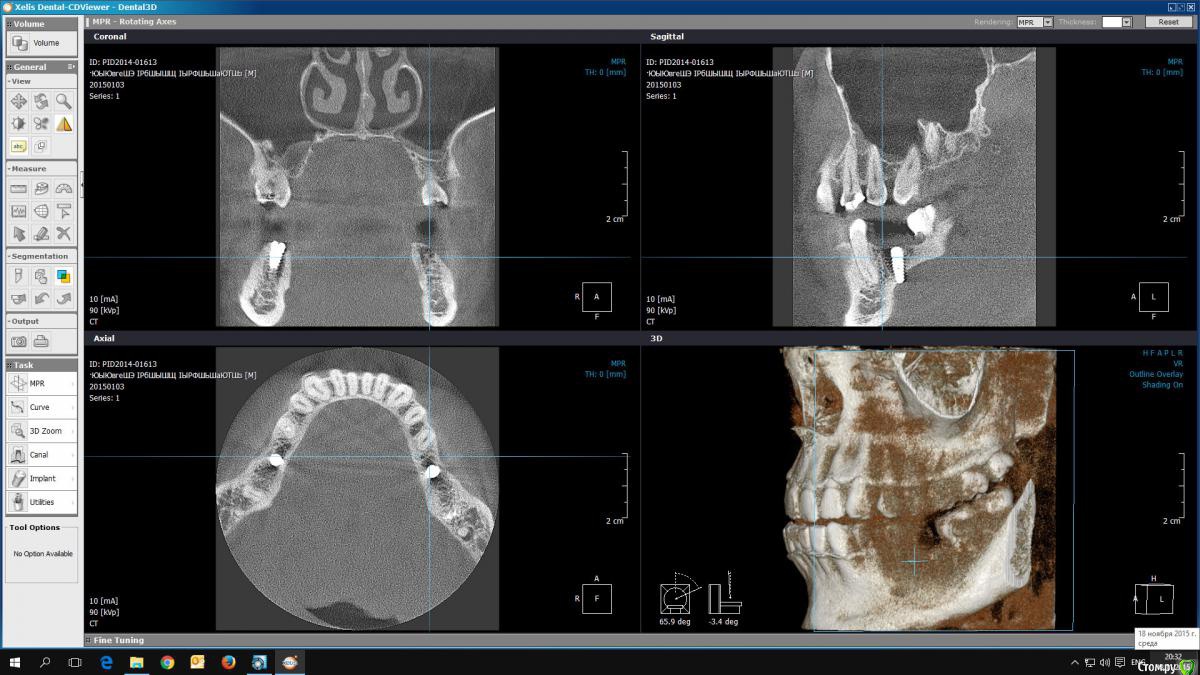

reloaded Опубликовано 18 ноября, 2015 Автор Поделиться Опубликовано 18 ноября, 2015 История имела следующее продолжение. Боли усилились, а температура, как ни странно, опустилась до 35. Врач посоветовал ждать до воскресенья. На следующий день начался отек, и мне стало трудно глотать. Я сказал врачу, что поеду в ЦНИИС. Он предложил приехать к нему и выкрутить имплант, что я и сделал. После процедуры мне дали на подпись бумагу, что имплант был удален по моей просьбе. Мне заявили, что по гарантии мне могут переделать только один раз. Я отказался подписывать, так как ни о чем не просил и просто изложил свои жалобы. Как мне теперь разобраться в этой ситуации? Имеет ли смысл сейчас делать КТ? И самое главное! Что означала странная резкая боль при сверлении и в этот раз, и год назад, как будто сверло вышло насквозь? На всякий случай, учитывая полную идентичность симптомов, прилагаю снимки предыдущей установки импланта. Большое спасибо за помощь! Ссылка на комментарий

reloaded Опубликовано 18 ноября, 2015 Автор Поделиться Опубликовано 18 ноября, 2015 Ссылка на КТ: https://cloud.mail.ru/public/2omg/mSkvnfCb7 Ссылка на комментарий